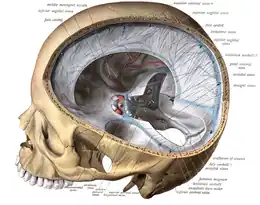

The dura mater extends into the skull cavity as the falx cerebri and tentorium cerebelli etc. | |

Folds and reflections

The dura separates into two layers at dural reflections (also known as dural folds), places where the inner dural layer is reflected as sheet-like protrusions into the cranial cavity. There are two main dural reflections:

- The tentorium cerebelli exists between and separates the cerebellum and brainstem from the occipital lobes of the cerebrum.[3]

- The falx cerebri, which separates the two hemispheres of the brain, is located in the longitudinal cerebral fissure between the hemispheres.[4]

Two other dural infoldings are the cerebellar falx and the sellar diaphragm:

- The cerebellar falx (falx cerebelli) is a vertical dural infolding that lies inferior to the cerebellar tentorium in the posterior part of the posterior cranial fossa. It partially separates the cerebellar hemispheres.

- The sellar diaphragm is the smallest dural infolding and is a circular sheet of dura that is suspended between the clinoid processes, forming a partial roof over the hypophysial fossa. The sellar diaphgram covers the pituitary gland in this fossa and has an aperture for passage of the infundibulum (pituitary stalk) and hypophysial veins.

Dura mater (spinal section) Diagrammatic representation of a section across the top of the skull, showing the membranes of the brain, etc.